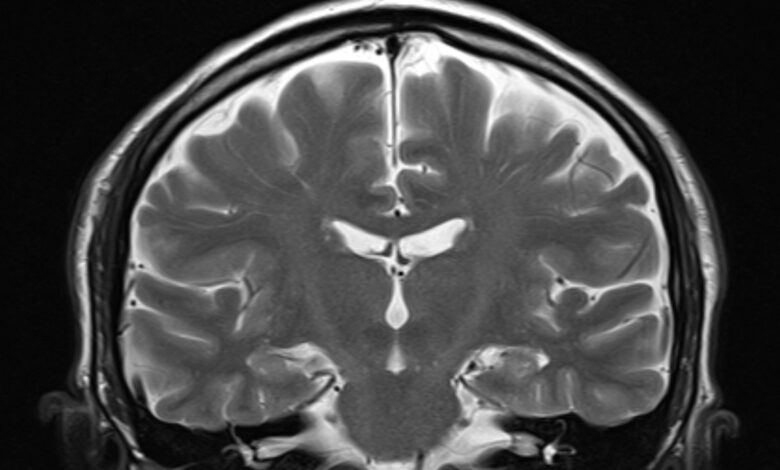

Vědci nyní mohou posoudit, jak rychle celé vaše tělo stárne na základě jediného snímku vašeho mozku, tvrdí vědci v nové studii.

Vědci, kteří zveřejnili svá zjištění 1. července v časopise Stárnutí přírodyvyvinuli měřítko biologického stárnutí založeného na MRI mozku. Tým říká, že nástroj může předvídat budoucí riziko kognitivního poškození a demence jednotlivce, chronické stavy, jako jsou srdeční choroby, fyzikální křehkost a předčasná smrt.

„Náš článek představuje nový způsob měření toho, jak rychle člověk stárne v daném okamžiku pomocí informací dostupných v jednom mozkovém MRI,“ řekl první autor Ahmad Haririprofesor psychologie a neurovědy na Duke University. „Rychlejší stárnutí zvyšuje naše riziko mnoha nemocí, včetně cukrovky, srdečních chorob, mrtvice a demence,“ řekl živé vědě v e -mailu.

Aby se vytvořil svůj nástroj, tým analyzoval mozkové MRI odebrané z této kohorty ve věku 45 let a spustil údaje o struktuře mozku – objem a tloušťka různých oblastí mozku a poměr bílé k šedá hmota – prostřednictvím algoritmu strojového učení.

Srovnali zpracované údaje o mozku s jinými údaji shromážděnými od účastníků současně, jako jsou testy fyzického a kognitivního poklesu, subjektivní zdravotní stav a známky stárnutí obličeje, jako jsou vrásky. Tvrdili, že větší pokles v těchto oblastech byl vázán s rychlejším tempem stárnutí, celkově a poté koreloval rysy mozkových dat s těmito metrikami. Říkali jejich výsledný model „Dunedin tempo stárnutí vypočtené z neuroimagingu“ nebo Dunedinpacni.

Hariri věří, že Dunedinpacni má potenciál být široce přijímán, protože typ MRI, které používá, je běžně shromažďován. Nyní je to otázka drcení dat a určování standardů toho, co odráží „zdravé“ a „špatné“ stárnutí, řekl.